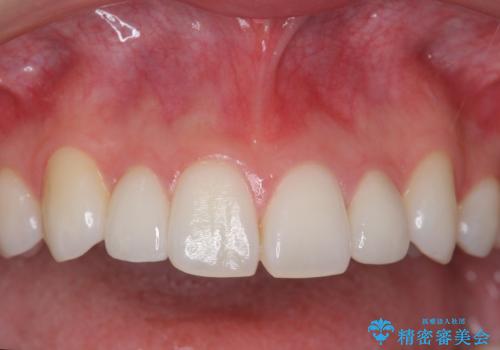

いきなりセラミックでかぶせるよりも手間をかけた分、自然な仕上がりになっています。

先に矯正治療をすることで、下の前歯を内側に入れることができ、上の歯のセラミックの幅や厚みを取ることができました。